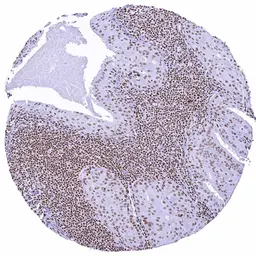

IHC-P analysis of human anal canal squamous cell carcinoma (SCC) tissue using GTX640917 SMARCA2 antibody [HMV337] HistoMAX™.

Squamous cell carcinoma with strong SMARCA2 immunostaining of tumor cells.